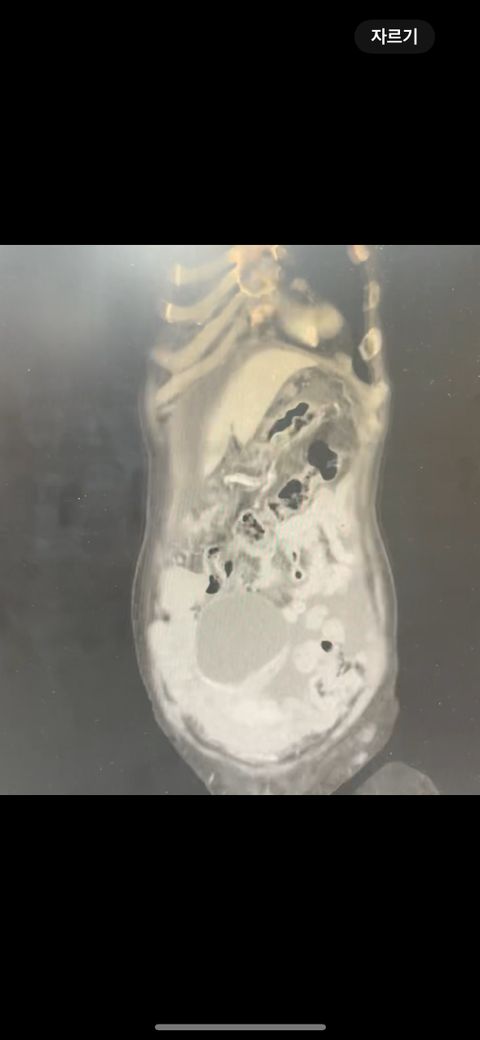

복부 ct 영상 판독부탁드립니다.!

결과는 3일 후 볼 예정인데 우선 영상만 받은 상태이고 너무 궁금한데 영상가지고 판독을 못해서요,,

이 사진가지고 확인할 수 있을까요 ?